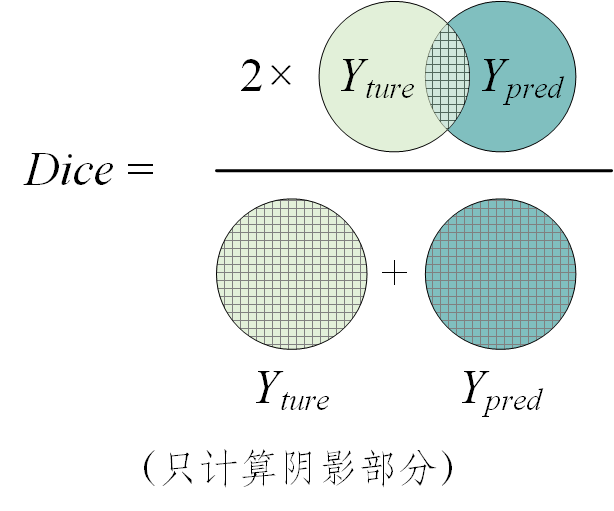

四、评价指标

赛会官方给出了两个评价指标,dice分数和豪斯多夫距离。其中,Dice分数比豪斯多夫距离更重要。

-

Dice分数

衡量两个集合的重合程度,是判断预测区间与Ground truth符合程度的主要指标

公式为: